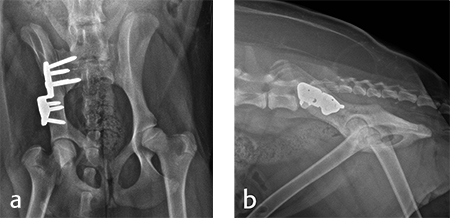

A 4-month-old female boxer puppy weighing 15.0 kg presented with bilateral hind limb weakness and reluctance to walk. Physical examination revealed bilateral hip instability (positive Ortolani sign) and severe pain on full extension of the hips. The neurological exam was normal. The radiographs revealed bilateral hip subluxation and a distraction index of 0.65 of the right hip and 0.6 of the left hip (Fig 7). Very mild osteoarthritis was seen and femoral head coverage by the dorsal acetabular rim was good (Fig 8). Angles of subluxation (10° R and 20° L) and reduction (30° R and 40° L) of the hips were measured under anesthesia.

For each surgical procedure, the patient was placed in dorsal recumbency to enable the pubic ostectomy. The patient was repositioned in lateral recumbency to perform the DPO. A left ilial osteotomy was performed caudal to the sacrum. A 25° DPO/TPO plate was attached to the caudal ilial segment using locking 3.5 mm screws in the three stacked combi holes. The caudal acetabular segment was rotated laterally until the cranial aspect of the plate was in contact with the lateral aspect of the cranial ilial segment. The osteotomy site was compressed and the plate was secured to the cranial ilial bone segment using a 3.5 mm cortical screw in the LCP combi hole in the cranial side of the plate. Three additional 3.5 mm locking screws were placed in the remaining stacked combi holes in the cranial segment of the plate (Fig 9).